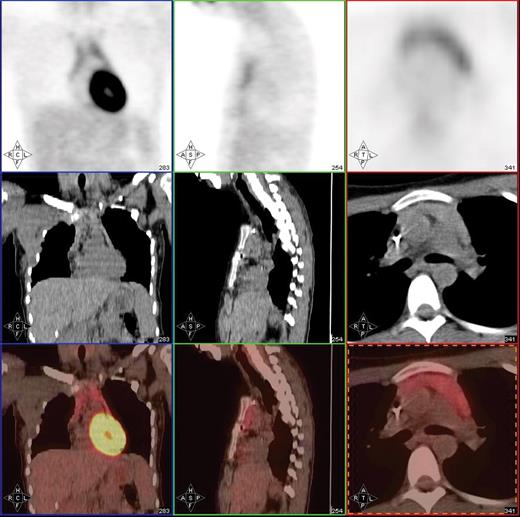

Post-treatment PET/CT scan in a 20-year-old patient with Hodgkin lymphoma showing thymic hyperplasia with otherwise no PET evidence of disease.

Post-treatment PET/CT scan performed 2 months after treatment with 8 cycles of AVD followed by involved field radiation therapy in a patient with stage IIA mixed cellularity Hodgkin lymphoma showing a PET-negative residual mass in the mediastinum measuring 4.2 × 2.9 cm. PET/CT was otherwise negative. This patient is currently without evidence of disease after 23 months of follow-up post therapy.